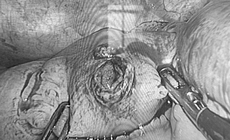

Loại bỏ khối u chung sống 10 năm gây liệt mặt

Camera bệnh viện - 08/10/2025 17:16SKĐS - Các bác sĩ Bệnh viện Tai Mũi Họng Trung ương đã thực hiện ca phẫu thuật, loại bỏ trọn vẹn khối u và bảo tồn tối đa chức năng, thẩm mỹ vùng mặt cho người bệnh.